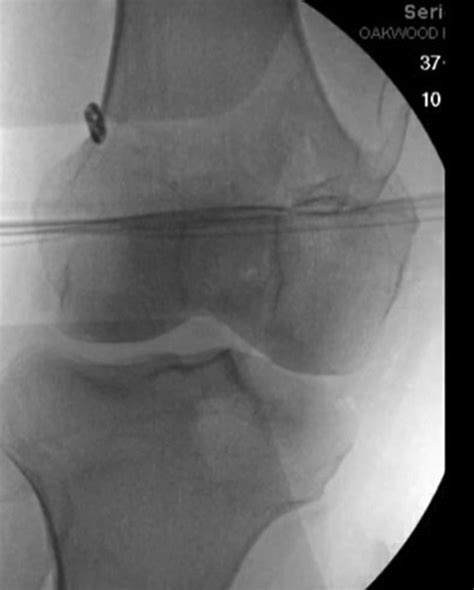

• Imaging Studies: X-rays, MRI, and CT scans can provide detailed images of the knee joint, helping to identify any structural abnormalities, fractures, or soft tissue injuries. MRI is particularly useful for visualizing the MPFL and other ligaments.

• Specialized Tests: In some cases, additional tests such as arthroscopy may be performed to directly visualize the knee joint and assess the condition of the MPFL and other structures.